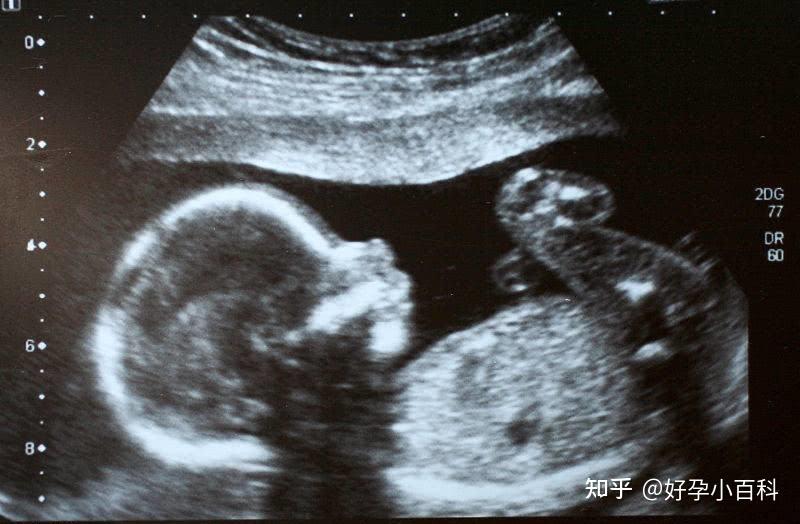

2、早孕期測量妊娠囊直徑(GSD)

在卵黃囊及胚胎尚不能顯示時,可通過測量妊娠囊的大小估計孕齡。常用的計算方法是:妊娠天數(d)=30天+妊娠囊直徑GSD(mm)。

例如當超聲測量妊娠囊平均直徑為5mm時,根據公式計算,孕齡為35天。本方法適用于孕7周內,因妊娠囊形態不規則,且受膀胱充盈程度的影響,測量值變異較大,故僅供參考。

3、早孕期頭臀長(CRL)

妊娠6-12周內,測量CRL是估計妊娠齡大小的最準確方法。6周初由于胚胎太小,測量不準確,但幾天后即可準確測量線狀胚芽。由于正常胚胎生長速度幾乎以1mm/d的速度線性生長,妊娠齡的大小約等于胚胎的長度(mm)加42天。即:妊娠齡(d)=胚長(mm)+42。也可采用下列公式計算孕周:妊娠齡(周)=CRL(cm)+6.5。注意:本計算方法適用于孕7-12周。

比如超聲測量CRL4.5cm,孕周=4.5+6.5=11周,另外雙胎妊娠時在統計學上用CRL計算和單胎妊娠沒有明顯差異,單雙絨毛膜也沒有明顯差異,需要注意的是雙胎時CRL在4-60mm的時候一致性較好。

2、根據早孕期B超推算

受孕后早期B超檢查,如孕45天B超檢查,孕70天B超檢查亦可以根據妊娠囊大小、頭臀長等數值,借助B超內的計算公式軟件估計胎兒大小,據此計算預產期也是較為準確的方法。